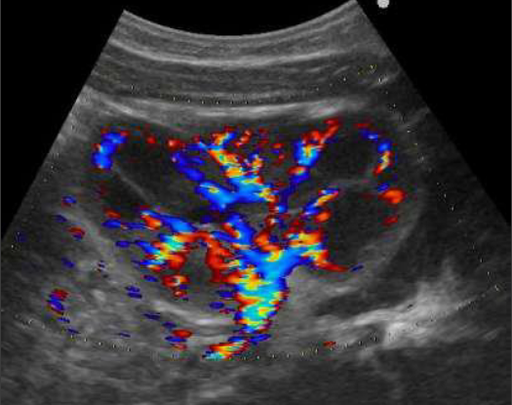

Imagerie des infections urinaires et du reflux vésico-urétéral

DESPRECHINS B. – ULG

Année académique 2021-2022

Urinaire Pédiatrique DES SPECIALITE